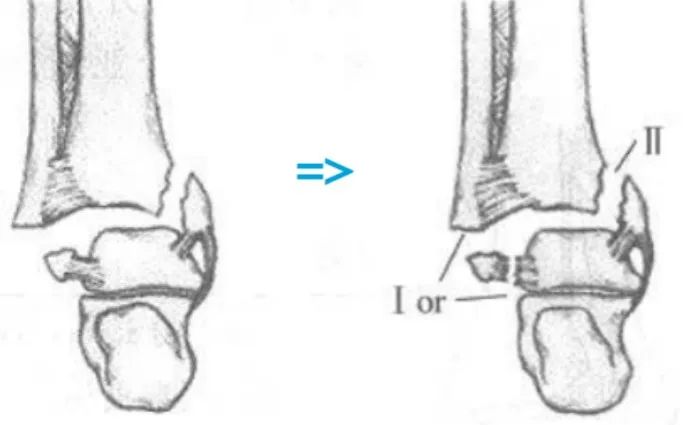

1、旋后(内翻)内收损伤(简称 SA)

损伤时,足呈旋后位,距骨内收,使踝关节外侧韧带紧张。

旋后内收损伤

Ⅰ度:首先发生的是外侧副韧带撕裂或者外踝的撕脱骨折,由于损伤发生于下胫腓联合远端,该韧带多保持完整。

I 度损伤 X 线显示:外踝间隙增宽,提示外侧副韧带撕裂,未见胫腓骨骨折,此型在 X 线上是隐匿的。

Ⅱ 度:内收的外力继续作用,内踝受内翻的距骨挤压作用,可造成内踝的垂直骨折,及胫骨远端关节面的内侧部分压缩骨折,如果合并其他方向的外力,有可能造成内踝的斜行骨折。

II 度损伤 X 线片显示:腓骨骨折在下胫腓联合水平以下,内踝垂直骨折;侧位 x 线片显示后踝无骨折。